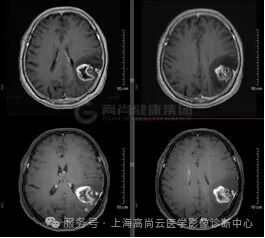

T1WI 增强

左顶叶可见团块状异常信号灶,大小约 38 mm×30 mm×35 mm,形态不规则,T1WI 呈稍低信号,T2WI 及 FLAIR 呈稍高信号,DWI 高信号,相应区域 ADC 呈稍低信号,ADC 值约 0.829×10-3 mm2/s,病灶内多发不规则囊变,相应区域 T1WI、DWI 呈低信号,FLAIR 呈低信号,T2WI 呈高信号,病灶局部 MRS 显示 Cho 峰增高,NAA 峰降低,Cho/NAA 比值约 3.45,增强时实性部分呈不规则、不均匀环形强化,部分呈延迟强化,相应区域灌注扫描显示 CBF 增高,邻近脑膜增厚、强化,周围可见大片水肿信号影环绕,邻近脑沟裂、脑池变浅,左侧脑室后角受压推移。

高级别胶质瘤(4 级)